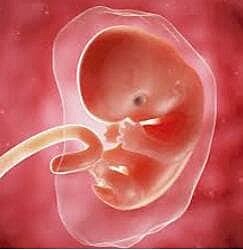

• 51-58 DÍAS – OCTAVA SEMANA

51-58 DÍAS – OCTAVA SEMANA

Aún es visible la cola del embrión.

Los ojos están abiertos y se logra percibir los pabellones auriculares.

Los dedos están unidos a una membrana.

Los parpados se juntan.

Comienza a diferenciarse los genitales externos.

Desaparece la membrana de los dedos.

El embrión ya tiene características humanas más evidentes.